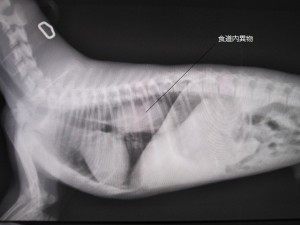

術後

術後のレントゲンです。

食道内異物はなくなりました。